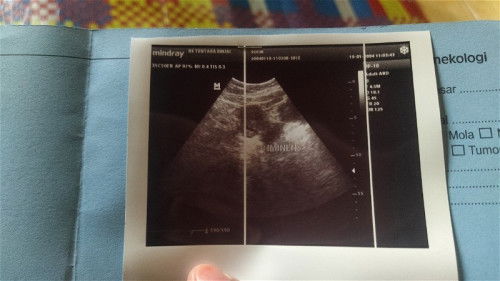

sama kek aku Bun keluar darah sama keluar gumpalan di USG ada kantong kehamilan posisinya pun msh bagus disuruh pertahankan duluπ₯±doain ya bun